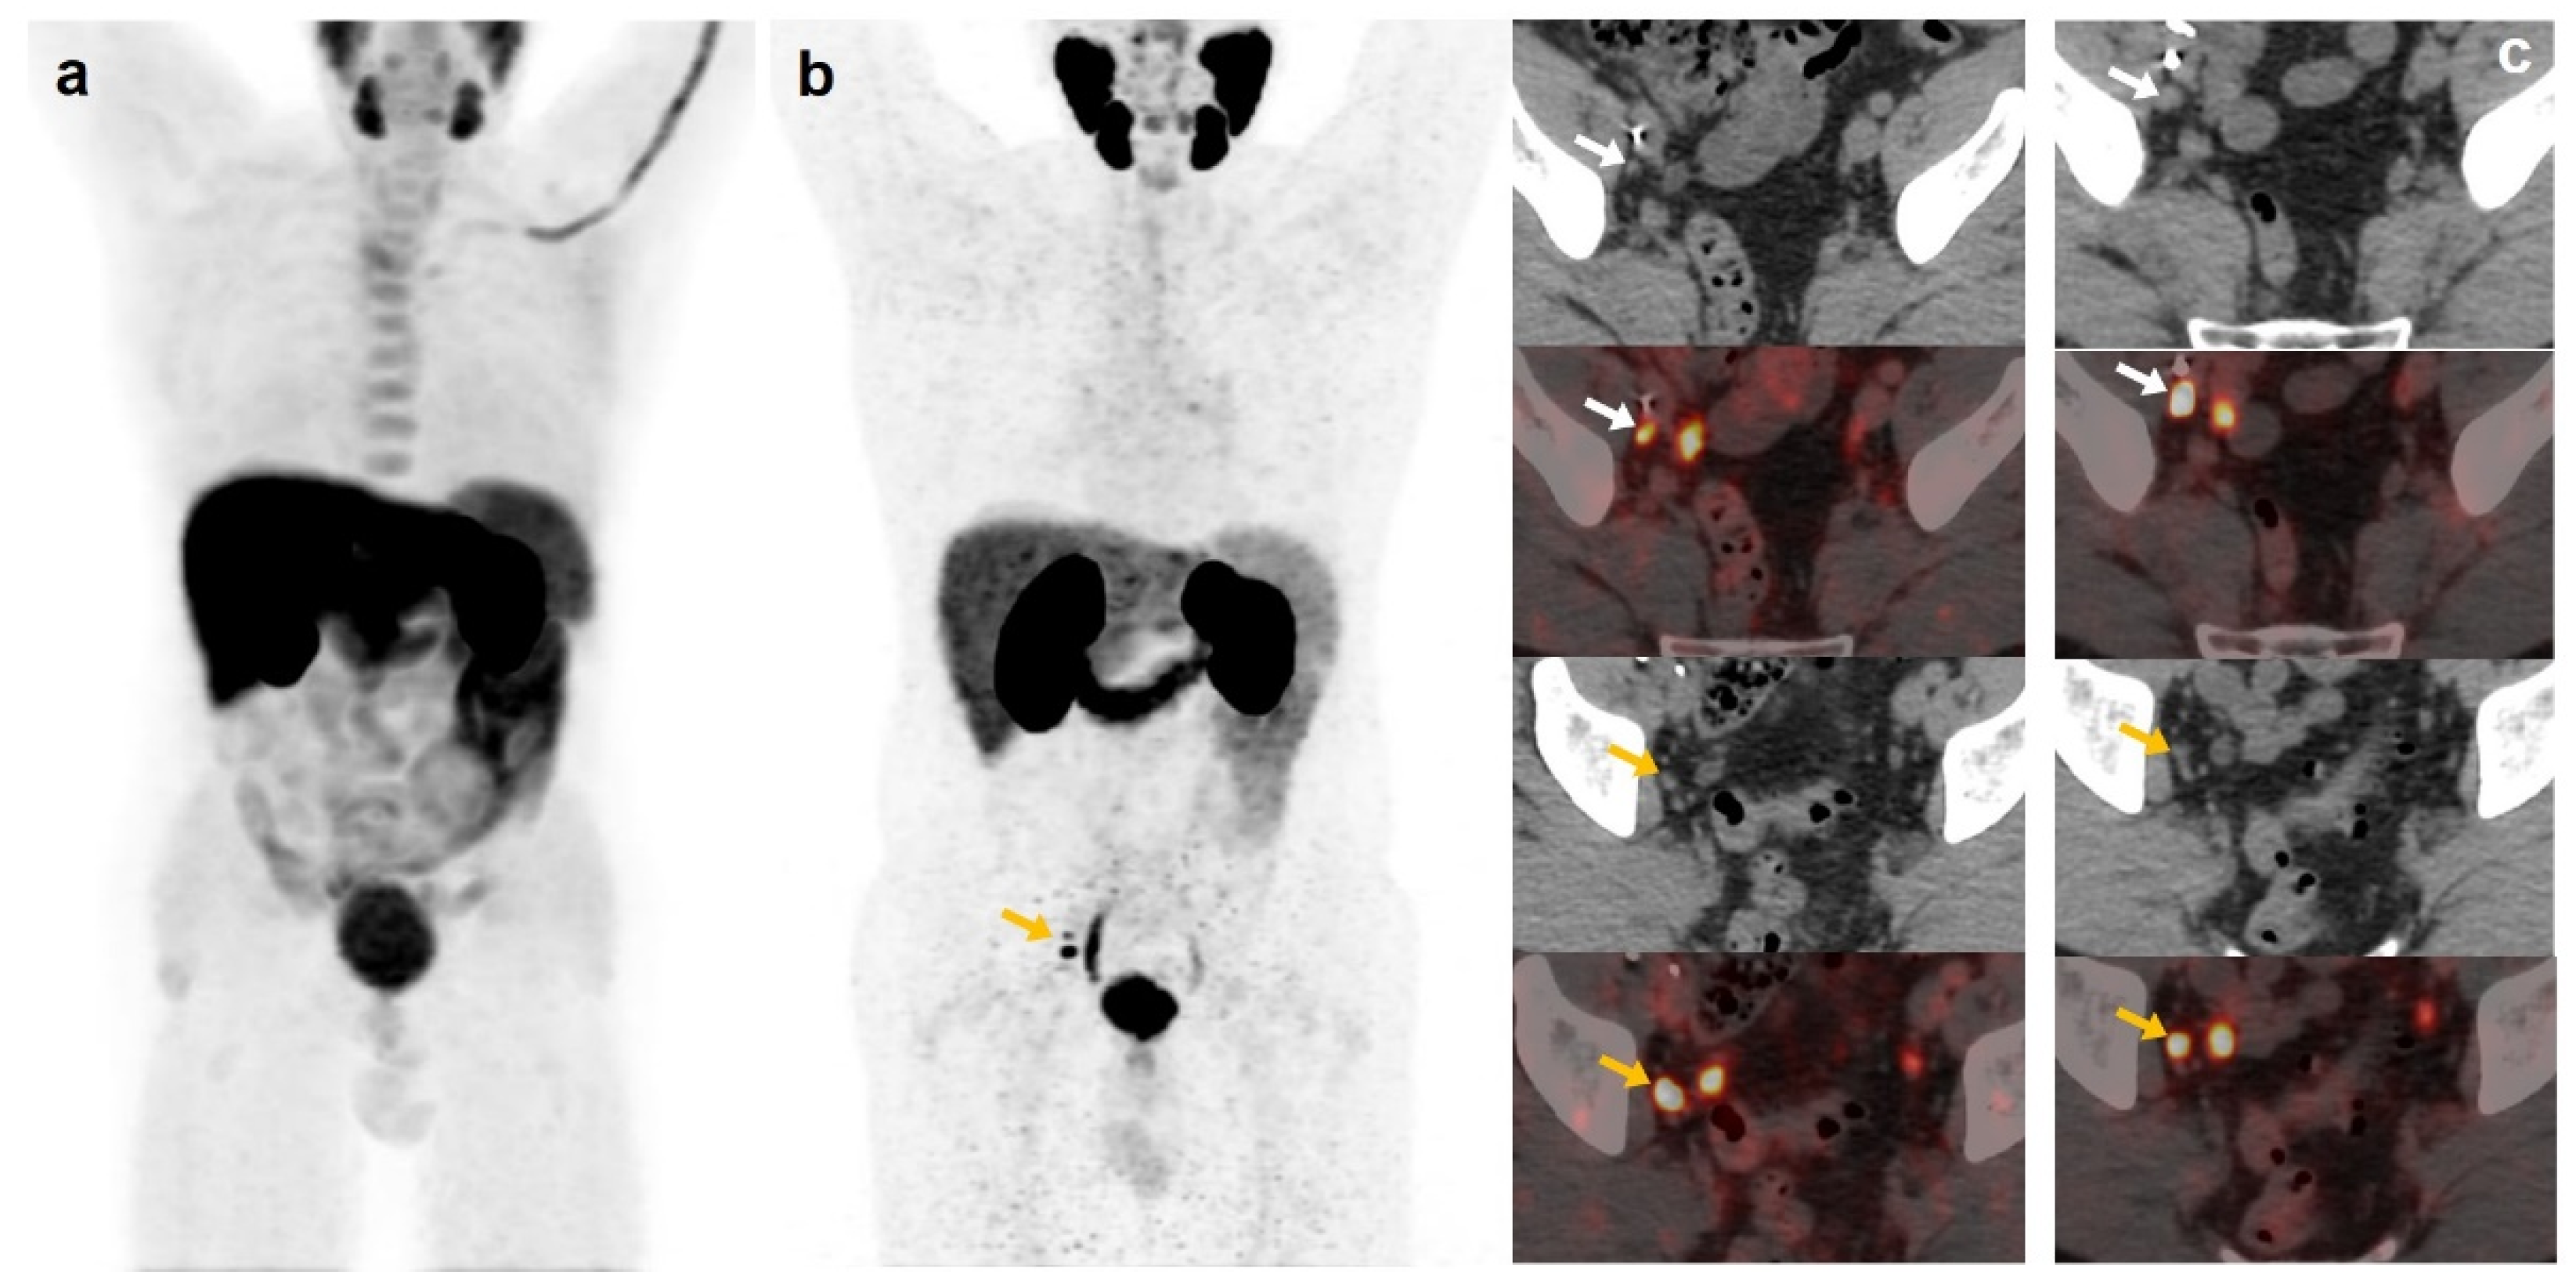

Figure 3.

55-year-old patient. Gleason 8 PCa treated with RP. First BCR treated with prostate fossa radiotherapy. Second BCR (PSA: 0.84 ng/mL, PSAdt 5.99 months, PSAvel 0.07 ng/mL/month). [18F]F-choline-PET/CT negative (a). [18F]DCFPyL-PET/CT (b), time window of twenty days, revealed two right external iliac lymph nodes metastases (white and yellow arrows). Lymphadenectomy was decided (escalation), without histopathological confirmation of malignancy. In follow-up, PSA progressed (2.07 ng/mL) and an additional [18F]DCFPyL-PET/CT (c) showed exactly same lymph nodes (white and yellow arrows). SBRT was administered decreasing the PSA level, reclassifying [18F]DCFPyL-PET/CT results as true positive.